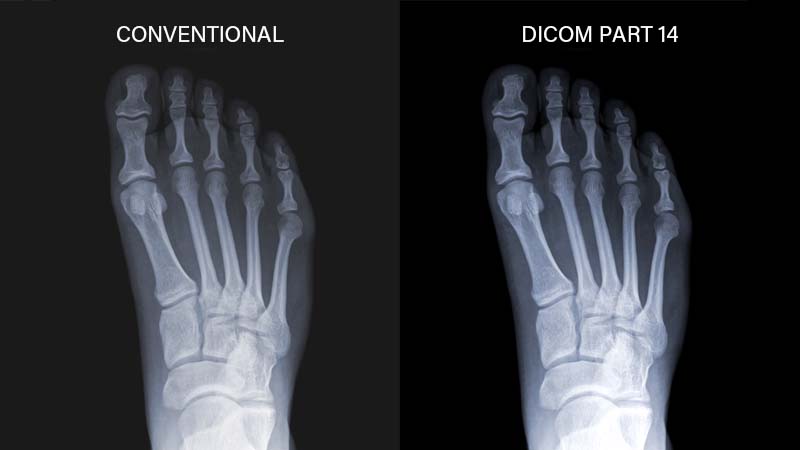

DICOM,中文稱為「醫療數位影像傳輸協定」,是一組通用的標準協定,此協定能確保在不同醫材設備間無縫共享和傳輸影像數據。一台符合 DICOM 標準的醫療級顯示器能夠清楚呈現不同灰階醫學影像,讓醫療人員得以進行更精確的診斷。

一台提供準確且清晰顯示灰階醫學影像的螢幕,必須符合 DICOM 影像模式標準。且在出廠時,每台螢幕需經過特殊校準,確保色彩和灰階的精確度,清晰呈現出每個細節。

AG Neovo MD 系列臨床檢視醫療顯示器,不僅搭載高畫質解析度和優異的色彩表現,且完全符合 DICOM 標準,提供清晰準確的 X 光、MRI 及 CT 掃描影像。此外,顯示器提供多種輸入/輸出連接埠以及符合人體工學的腳座設計,成為醫療專業人員的理想診斷幫手。